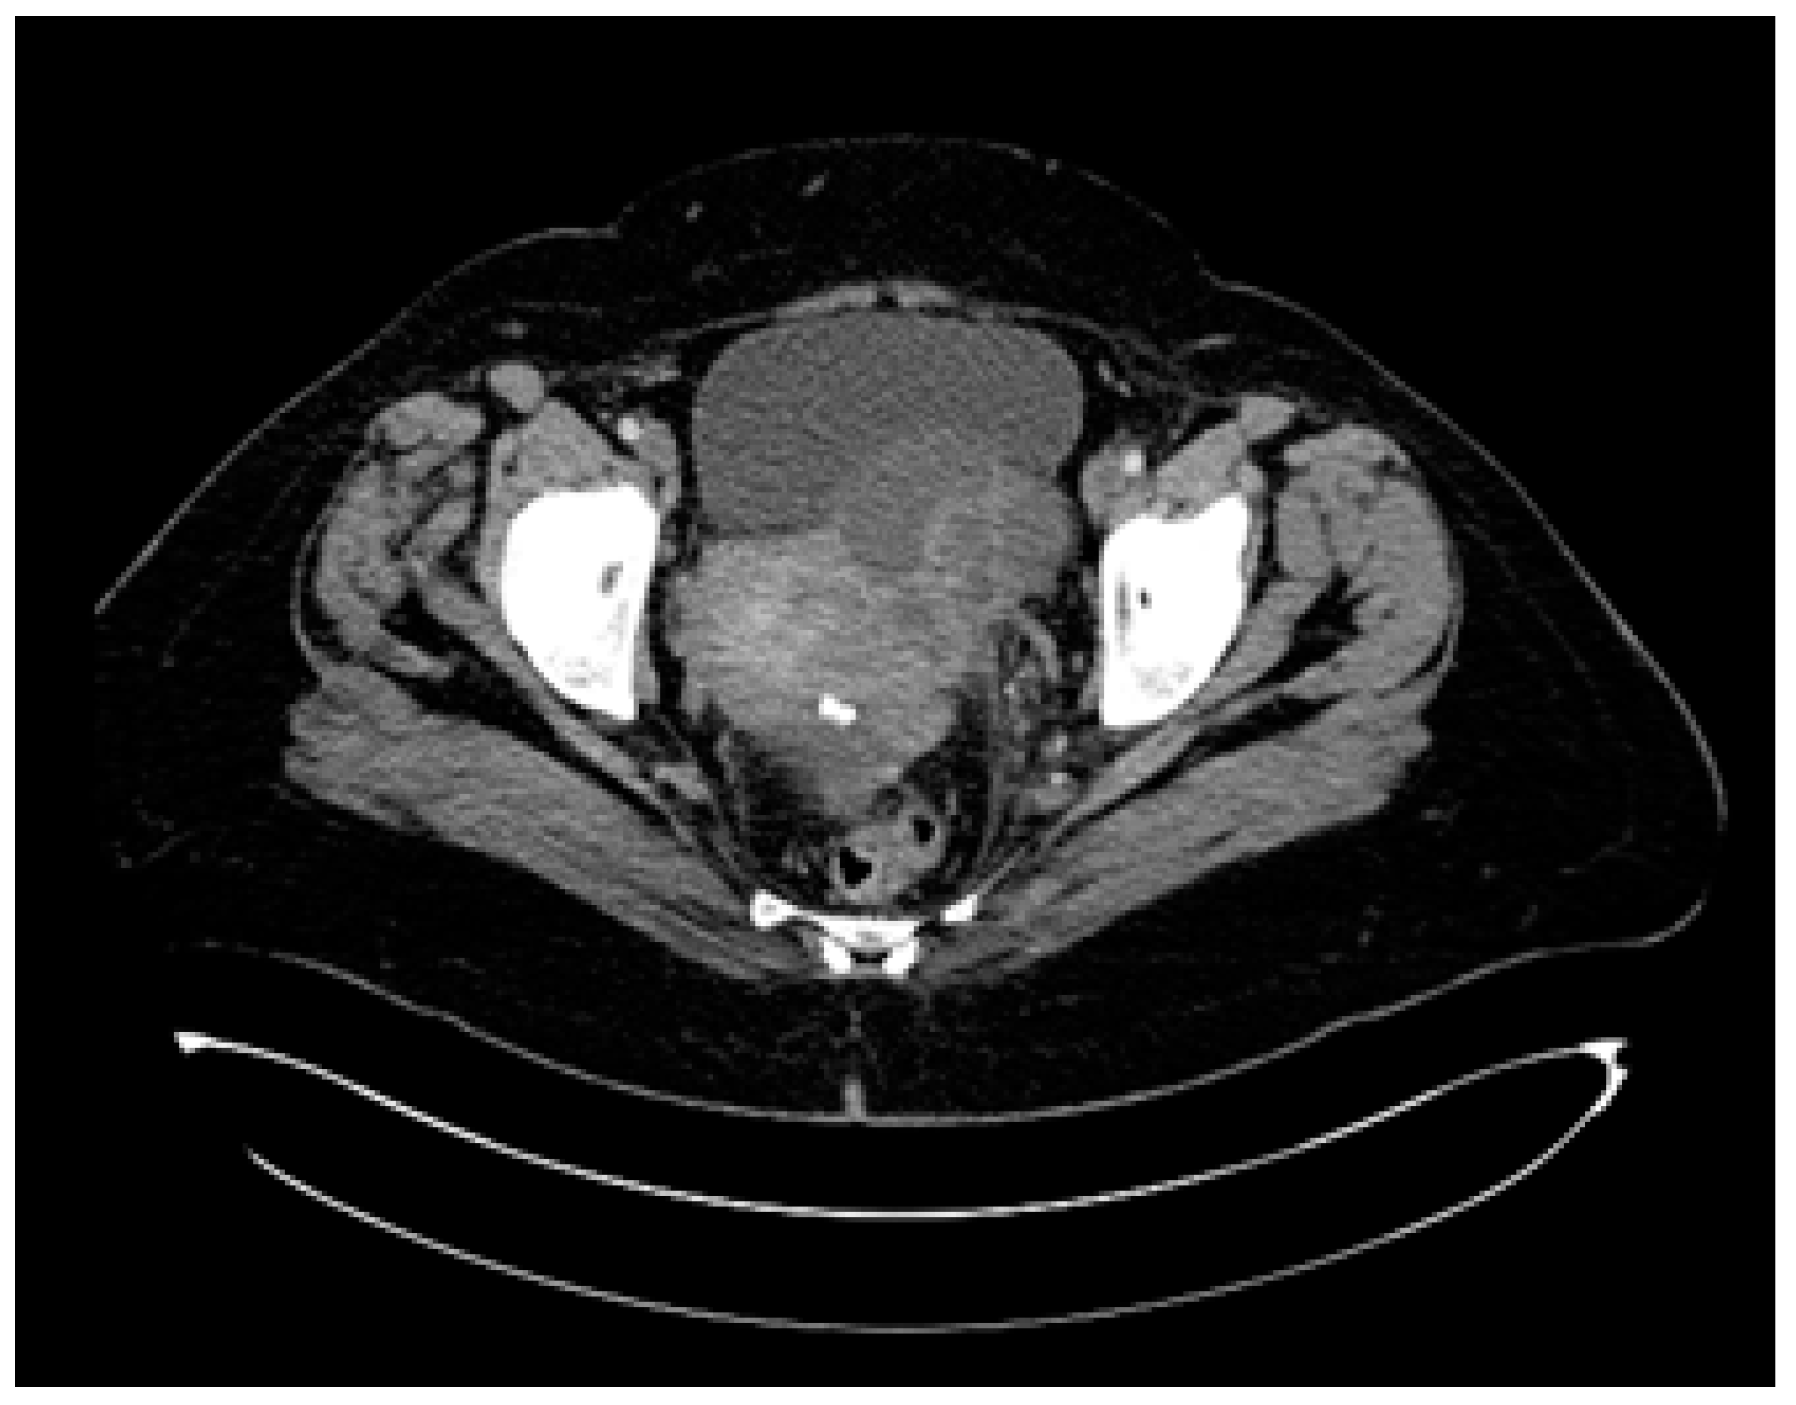

Between September 2015 and February 2016, six cycles of Carboplatin (AUC 5) and Paclitaxel (175 mg/m2) were administered every 3 weeks, with good clinical tolerance and without hematological toxicity. A post-chemotherapy CT scan described a partial response according to RECIST 1.1. The CT imaging findings revealed a significant change in the patient’s tumoral burden, demonstrating a left adnexal tumor measuring 75/56 mm with malignant features and indistinct boundaries from the uterine fundus, suggesting direct invasion or close association. In a positive turn of events, the previously noted pleural effusion had resolved, and there was a complete disappearance of ascitic fluid, indicating a favorable response to the recent therapeutic intervention (Figure 8). After six cycles of chemotherapy, the CA-125 level was 9.04 IU/L.

Figure 8.

The first follow-up (CT scan of the thorax and pelvis, March 2016) showing partial response to treatment.

A significant result within the clinical narrative of this case, the detection of deleterious BRCA1 missense alterations in a compound heterozygous state, c.181T>G (p.Cys61Gly), in September 2016, set the stage for the introduction of Olaparib the following month. The therapeutic efficacy was confirmed via biannual CT scans of the thorax, abdomen, and pelvis, which indicated a positive outcome, achieving complete remission of the disease (Figure 9).

Figure 9.

Complete response assessed through CT from August 2018 to September 2020.